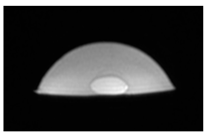

| Ultrasound |  |  |  |

| Ultrasound |  |  |  |

| Ultrasound |  |  |  |

| Ultrasound |  |  |  |

| Ultrasound |  |  |  |

| Ultrasound |  |  |  |